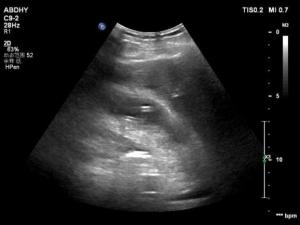

在家属协商,充分告知并签署知情同意书后,晚11点超声介入团队黄毅主任和王思翰医师为患者在超声科介入室进行了超声引导下经皮经肝胆囊穿刺置管引流术。过程顺利,术中抽出灰黄色浑浊液体约70ml,术后患者腹痛症状明显减轻,安返病房。